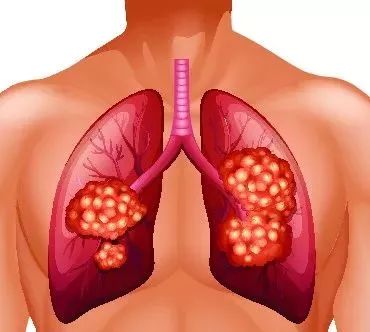

- 非细胞肺癌复发 图片合集